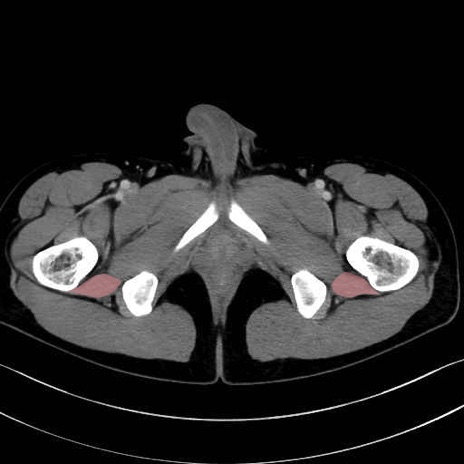

大腿方形筋 (Quadratus femoris)